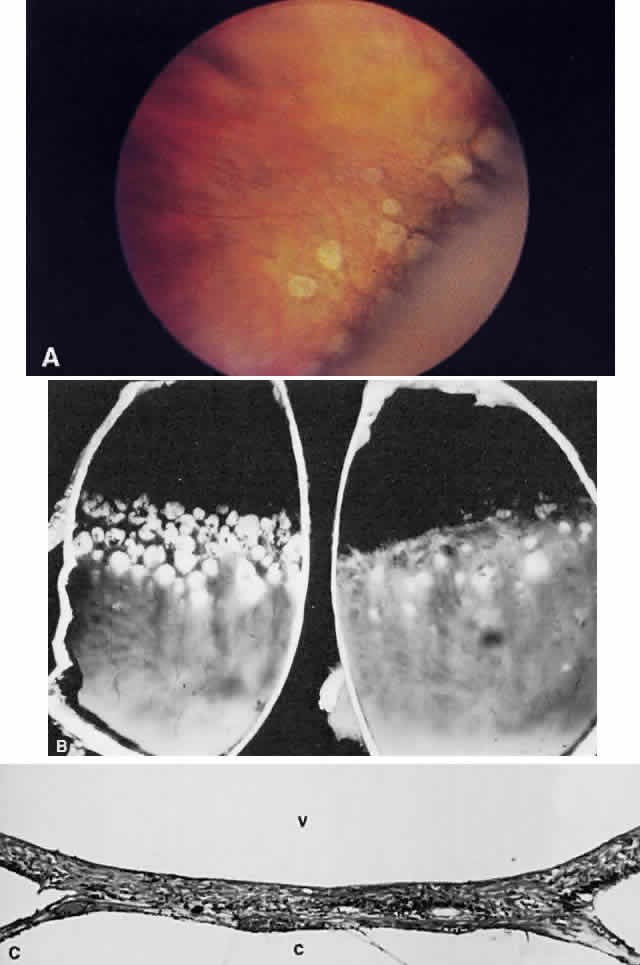

Necrotic retina has a white appearance. Necrosis may result from a variety of inflammatory conditions, including viral, fungal, and protozoal (Toxoplasma) retinitis. Each type of retinitis appears, in part, as a white retinal lesion. Cytomegalovirus retinitis (Fig. 24) resembles a pizza pie with an admixture of white (retinal inflammation) and red (hemorrhage) colors (Fig. 25). The retinal abscesses of fungal retinitis are white. Likewise, the satellite lesion of retinochoroiditis caused by active Toxoplasma (the choroidal inflammation is merely in response to the primary retinal infection) is white (Fig. 26). The white appearance of a lesion from inactive Toxoplasma results from the destruction of neurosensory retina, retinal pigment epithelium, and choroid to permit a direct view of the sclera (Fig. 27). Necrosis in retinal-derived neoplasms is white; the appearance of regressed (necrotic) retinoblastoma often is described as “cottage cheese.”10

Fig. 24. A. Histologic section of cytomegalic inclusion retinitis. The characteristic inclusions cannot be seen at this magnification. Compare the appearance of viable healthy retina (left of arrow) with necrotic retina (right of arrow). The admixture of necrotic retina (clinically white) with hemorrhage (clinically red) accounts for the ophthalmoscopic appearance of this entity. B. Cytomegalovirus retinitis. Histologic section of sensory retina demonstrating massive necrosis involving all layers. (Courtesy of Ralph C. Eagle Jr, MD, Philadelphia, PA)

Fig. 25. Fundus photograph of cytomegalovirus retinitis with the classic admixture of retinal infection (white) and hemorrhage, giving the so-called “pizza-pie” appearance.

Fig. 26. Fundus photograph of toxoplasmosis chorioretinitis scar with white (active) satellite lesion.

Fig. 27. Fundus photographs of quiescent toxoplasmosis chorioretinitis scar. The white center is the result of destruction of the neurosensory retina, retinal pigment epithelium, and choroid, leaving only the sclera in view.